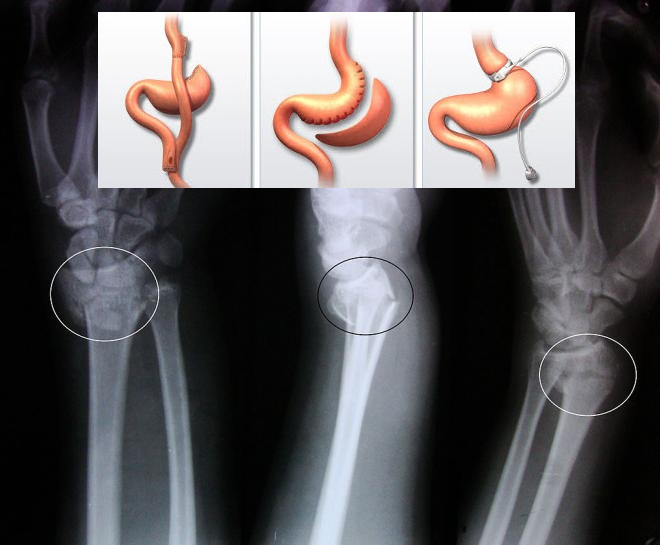

Переломы чаще встречались у тех, кто подвергался мальабсорбтивным операциям, предотвращающим усвоение пищи. У таких пациентов вероятность появления переломов увеличивалась на 47%, этот показатель оставался высоким в течение 12 лет после операции. Чаще всего люди ломали лучевые, локтевые, плечевые кости, а также бедренные и берцовые.